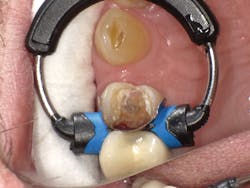

In Case Two, we'll replace an old composite inlay (figure 6). As in the first case, the LiteTouch erbium YAG laser was used to remove the inlay without anesthetic. As the decay had spread subgingivally on the interproximal surface, a small gingivectomy was needed to access the final gingival margin. After placing some topical anesthetic on the soft tissue and using a low energy setting, the Lite Touch laser was used to remove the excess interproximal soft tissue (figure 7). A sectional matrix band and newly designed Fusion Wedge (Garrison) was placed, and the band lightly burnished against the adjacent tooth (figure 8). A self-etch adhesive technique using Futurabond U was used. After curing the adhesive, a bulk-fill flowable (x-tra base, Voco) was used in the floor of the box. Using a flowable bulk fill in this fashion virtually assures you of a tight gingival seal at the bottom of the proximal box. Next, Admira Fusion Opaque shade OA3 was used to mimic the dentin (figure 9), followed by placement of the final enamel layer of material. The finished restoration exhibits a high polish with a close-up intraoral appearance that mimics a ceramic inlay (figure 10).

Figure 6

Figure 7

Figure 8

Figure 9

Figure 10